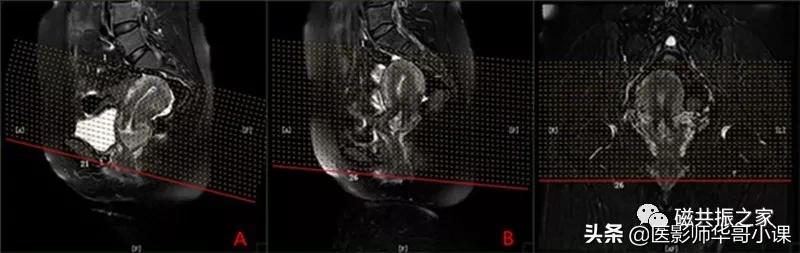

冠状位: COR T2 FS FSE 冠状面T2脂肪抑制序列

在横轴位和矢状位上定位,在矢状位上找到显示子宫全长最好的层面,如需了解宫颈病变,使定位线平行于宫颈管长轴(图A),如需了解子宫内膜病变,使定位线平行于子宫内膜长轴。在横轴位上找到显示子宫最大的层面,使定位线平行于当前子宫内膜长轴,扫描范围包括整个子宫及两侧附件,需包括整个病变范围。

添加上下饱和带,减小血管搏动伪影。

FOV不宜过大,采用FS(频率选择饱和法)技术时需添加局部匀场。

使用过采样技术,相位编码为左右。

冠状位是显示卵巢及子宫附件较为理想的方位。